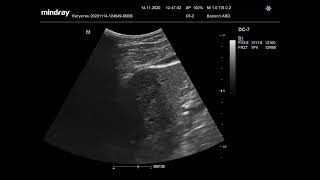

Ультразвуковая диагностика. Доктор Иогансен. Видеопримеры. Выпуск 5. Киста поджелудочной железы.

Представлены видеопримеры кисты головки поджелудочной железы, выявленной при ультразвуковом исследовании. Ссылка на Дзен: https://dzen.ru/doktor_jogansen